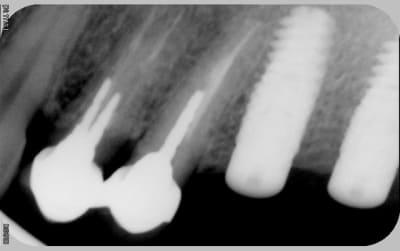

voici les radios le jour de la pose

le krestal doit être en crestal et non en infra-osseux: il s'agit d'une connectique à plat et non d'un cône morse.

18/06/2010 à 17h38

Je reviens là dessus car çà me semble être la clef

il me semble que sur le 1° cas présenté,la partie biseautée de l'implant est enfouie et que la cratérisation est nulle, idem pour l'implant mésial du dernier cas.

Sur son site Tekka préconise de mettre la partie supérieur de l'implant en juxtacrestal , donc le biseau est infraosseux...

J'avais rencontré le même pb sur un cas que j'avais présenté sur ce forum sur des IDcam et l'on m'avait fait remarqué à raison que l'enfouissement de l'implant distal était insuffisant, résultat a 6 mois cratérisation mésial et distal du dernier implant et à un an stabilisation .

Tu remarqueras que le biseau mésial de l'implant mésial qui a été correctement enfoui n'a pas bronché.